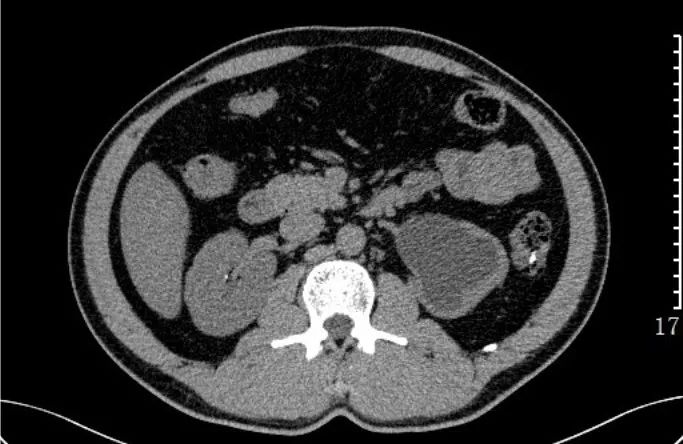

肾结石:CT平扫,右肾见不规则鹿角状高密度影,为铸型结石。

输尿管结石:CT平扫,左肾及左输尿管扩张积水,下段输尿管内可见小结节状高密度影。另见右肾小结石。